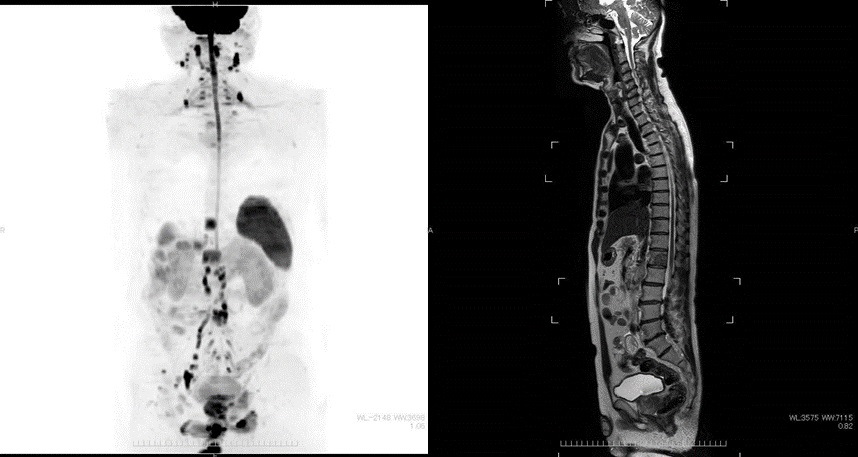

DWIBS法を使用した全身拡散強調MRIは、特に前立腺がんに多い骨転移に対して大変有効です。 そのため、前立腺生検により前立腺がんが確定した後の治療方針を決めるため転移の有無を確認するなどの目的にて行います。 また、前立腺がん治療後の再発や治療効果を評価するためにも撮影します。 前立腺癌以外にも、泌尿器がんの転移検索にも有効な検査です。